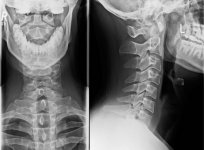

Hier ist noch eine Aufnahme von der Halswirbelsäule. Mir ist gesagt wurden damit sei auch alles ok.